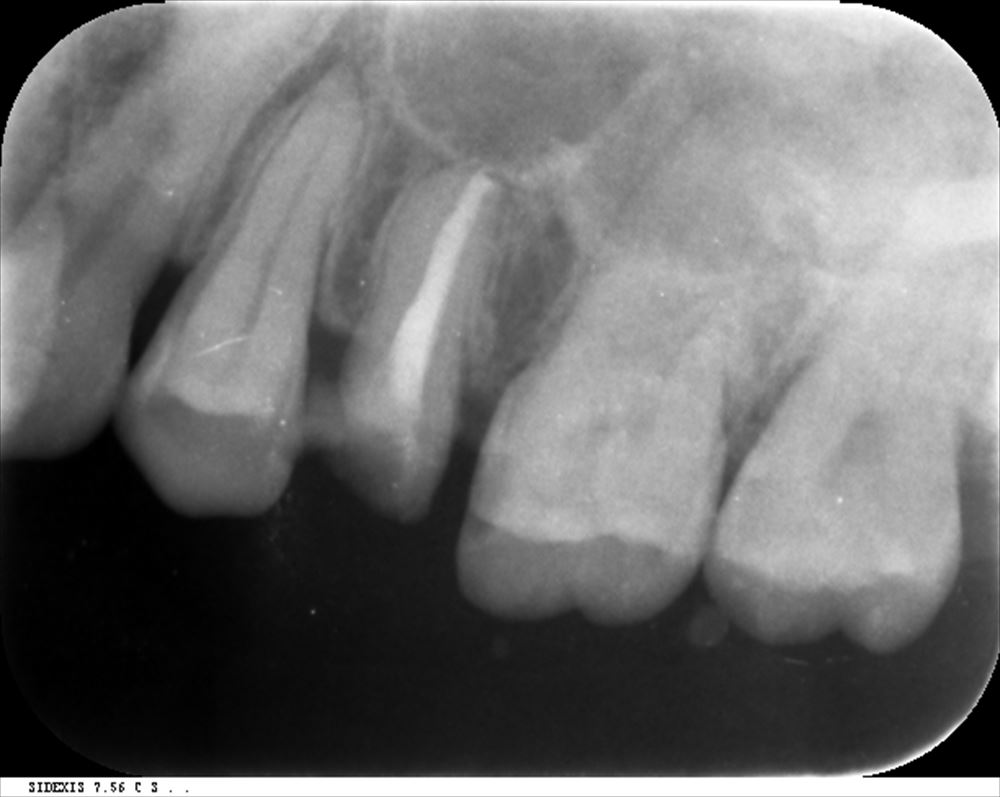

術前

根管内に綿栓

徹底的に綺麗にして根管充填。シーラーはMTAで工夫。

術前はこんな。上顎洞まで腫れていました。